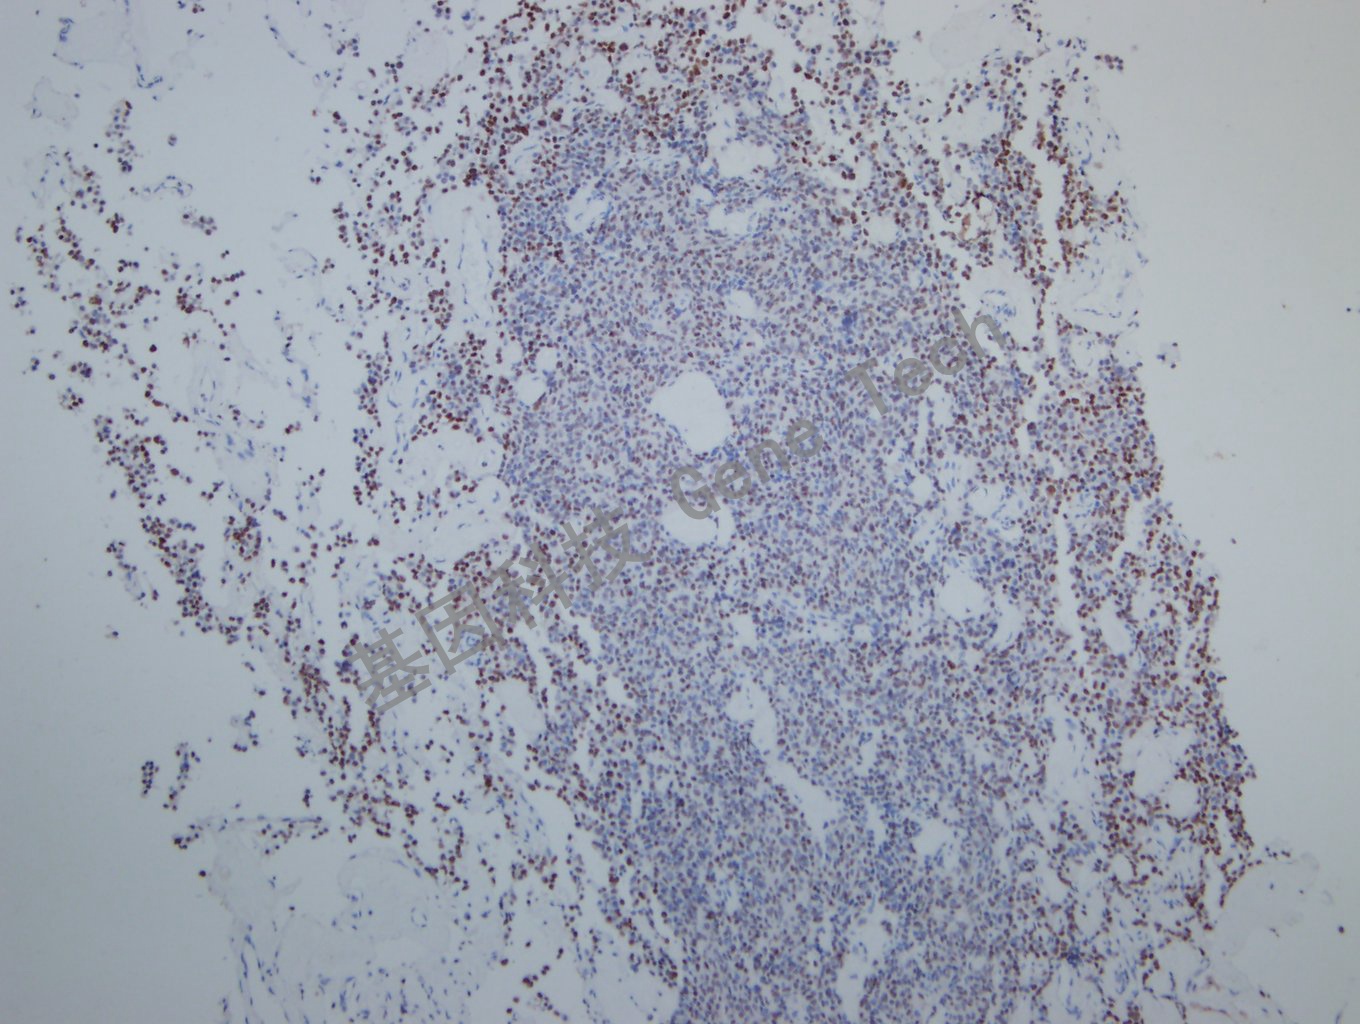

垂体瘤石蜡切片,用 PIT-1(GT2319)染色,细胞核阳性,DAB 显色。